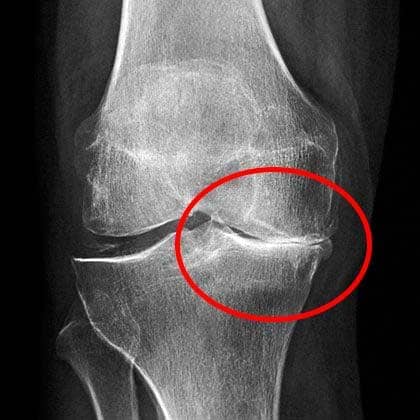

Imagen 3

Las radiografías mostraban un serio desgaste en las articulaciones.